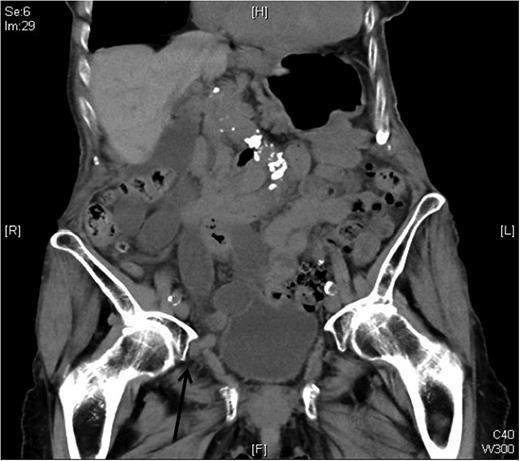

Computed tomography (CT) scan revealed an obturator hernia on the right side with a herniated small bowel loop with early signs of incarceration (Fig. 1).